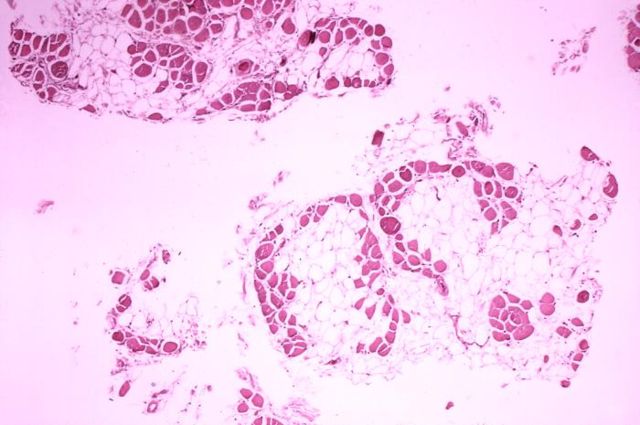

English: Histopathology of gastrocnemius muscle from patient who died of pseudohypertrophic muscular dystrophy, Duchenne type. Cross section of muscle shows extensive replacement of muscle fibers by adipose cells.